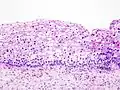

Absolutně nejčastějším typem karcinomu děložního hrdla je epidermoidní karcinom, který se postupně vyvíjí z místního růstu epitelu, přes jednotlivé stupně dysplasie až do pravé prekancerózy. Stádia prekancerózy se označují zkratkou LSIL nebo HSIL (low grade a high grade) a neléčená se mohou vyvinout zpočátku v lokální (karcinom in situ), později invazivní karcinom. Změny typicky začínají v místě přechodu dlaždicového epitelu děložního hrdla do cylindrického epitelu cervikálního kanálu. Výskyt dysplazií se odhaduje na 3 až 5 % dospělých žen.

Patologie

Jako karcinom děložního hrdla je různorodá skupina zhoubných nádorů. Nejčastější je rohovatějící a nerohovatějící epidermoidní karcinom (80 % případů) a adenokarcinom (15 % případů).[8] Výskyt adenokarcinomu se v poslední době zvyšuje, je spojený s chronickým zánětem děložního hrdla a zvýšenou hladinou estrogenu, vyznačuje se rychlejším růstem (i během jednoho roku) a má o něco horší prognózu (vyšší pravděpodobnost recidivy, tendence k infiltrativnímu růstu, problematičtější histologická i zobrazovací diagnostika).

Specifickou formou adenokarcinomu s 3% výskytem je tzv. adenoma malignum. Ačkoliv je to dobře diferencovaný mucinózní adenokarcinom, má velmi špatnou prognózu: rychle metastazuje, špatně reaguje na radio- i chemoterapii a navíc se problematicky diagnostikuje. Má totiž podobný vzhled jako běžné a nezhoubné cysty děložního hrdla. Tento typ nádoru je častý u pacientek trpících Peutzovým-Jeghersovým syndromem.[9]

K vzácnějším typům karcinomu děložního hrdla dále patří prognosticky špatný adenoskvamózní karcinom (3% výskyt). Ostatní jsou vzácné a rovněž většinou prognosticky nepříznivé: malobuněčný karcinom a další neuroendokrinní nádory.

Karcinom děložního hrdla většinou vzniká na rozhraní dlaždicového epitelu, který pokrývá plochu hrdla obrácenou do pochvy, a cylindrického epitelu, který vystýlá kanál děložního hrdla, spojující pochvu s dutinou dělohy. Většinou roste exofyticky, tedy ve formy polypu směrem do pochvy, ale není vzácná ani endofytická forma – ať již ve formě vředu nebo expanze šířící se směrem k tělu dělohy.